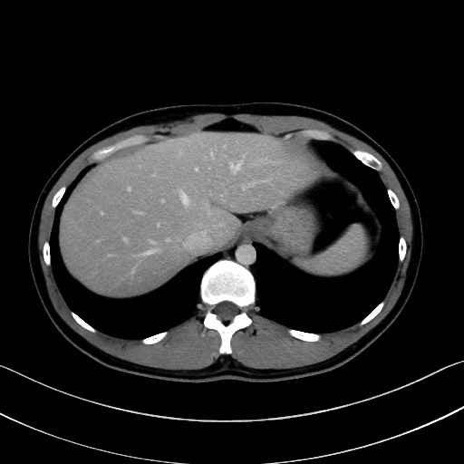

広背筋 (Latissimus dorsi)